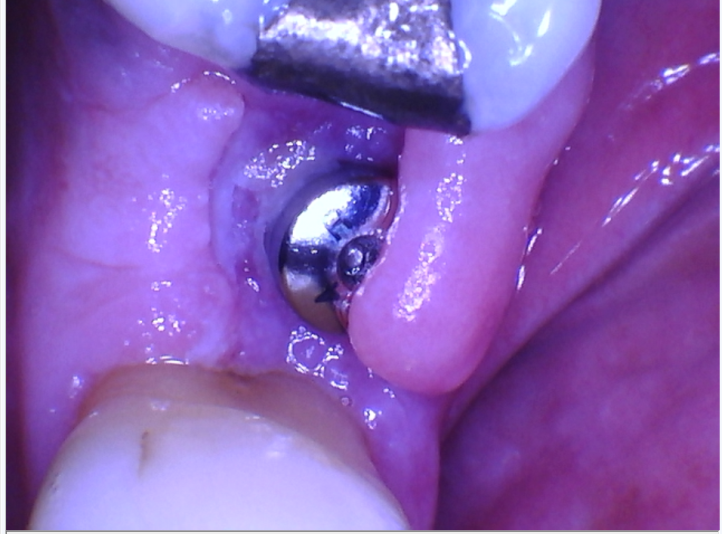

1st picture – Immediate day of placement post op

Placed a 5.0 x 7.0 Hiossen implant at #4 site. Every thing seemed to be going well, undersized my osteotomy by 1x (3.5). Placed the implant to 40 Ncm. Felt pretty confident so placed a healing abutment. Sutured with 4-0 silk, went with a horizontal mattress and 2 uninterrupted.

At the post op visit, noticed some purulence around the healing abutment along with the buccal tissue being flappy without any kind of closure. Also took a PA and noticed a distinct RL around the implant. Shit sucked.